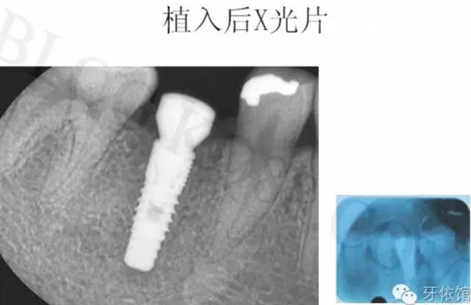

術(shù)后三個月的X光片。

連接印模帽后拍x光片,檢查印模帽與種植體之間是否緊密相連。